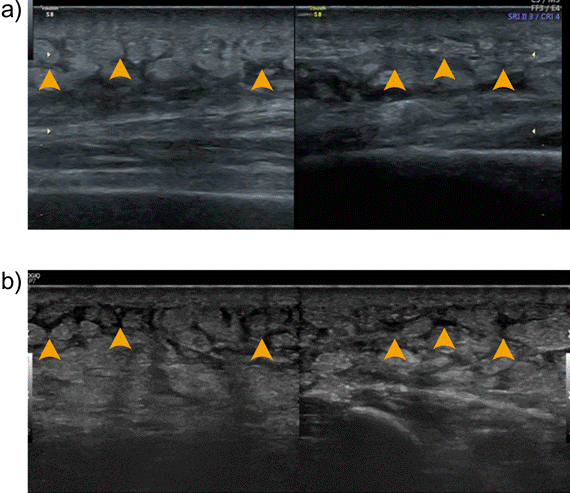

O exame de ultrassom apresentou uma imagem com a área de fibrose mais difusa após a intervenção (Figura 5), representando uma melhora do padrão de rigidez. Além disso, a paciente relatou como feedback as seguintes impressões: “sensação de redução do peso do membro, pele menos esticada e região mais amolecida ao toque”.

Figura 5. Comparação entre as imagens do ultrassom da região da fibrose do antebraço esquerdo da paciente: a) pré-intervenção (antes do uso da Fibro Placa) e b) pós-intervenção (imediatamente após as 18 sessões de tratamento). Imagem a): placa fibrótica bem delimitada, acompanhada de acúmulo localizado de líquido anecoico adjacente à área fibrótica. Imagem b): Fragmentação parcial da placa fibrótica, evidenciada por descontinuidade nos ecos hiperecogênicos que compõem a fibrose e melhor distribuição do líquido intersticial: diminuição do acúmulo local e dispersão mais homogênea do fluido no tecido subcutâneo. Setas amarelas: indicação comparativa entre as mesmas regiões da imagem a) e b)